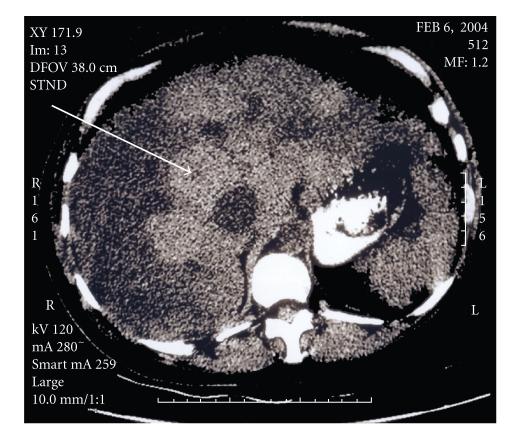

High-output cardiac failure secondary to hepatic involvement is a rare complication of hereditary hemorrhagic telangiectasia (HHT). Here we report a 43-year-old woman who presented at 29 weeks gestation of her second pregnancy with complications of right-sided heart failure and preterm labor. After delivery via cesarean section, the patient was found to have intrahepatic arteriovenous malformations through non-invasive imaging. Subsequently, a family history of vascular malformations and epistaxis was elucidated and a diagnosis of HHT was made. This case is presented, along with a review of the literature and discussion of hepatic involvement in HHT with particular focus on the pregnant patient.

继发于肝脏受累的高输出性心力衰竭是遗传性出血性毛细血管扩张症(HHT)的罕见并发症。我们在此报告了一位 43 岁的女性,她在第二次妊娠 29 周时因右侧心力衰竭和早产并发症就诊。经剖宫产分娩后,通过无创影像学检查发现患者存在肝内动静脉畸形。随后,发现存在血管畸形和鼻出血的家族史,并诊断为 HHT。本文呈现了该病例,并对文献进行了回顾,讨论了 HHT 中的肝脏受累,特别关注了孕妇患者。